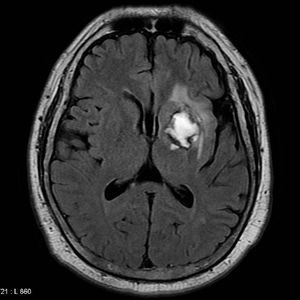

Subacute hemorrhagic stroke MRI

Brain MRI of a patient suffering from subacute hemorrhagic stroke. It results from a weakened vessel that ruptures and bleeds into the surrounding brain. The blood accumulates and compresses the surrounding brain tissue.